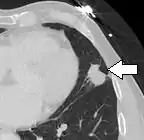

- Margin morphology: a spiculated margin is a risk factor for cancer.[8] Benign causes tend to have a well defined border, whereas lobulated lesions or those with an irregular margin extending into the neighbouring tissue tend to be malignant.[10] In particular, spiculations are highly predictive of malignancy with a positive predictive value up to 90%.[9] Also, a "notch sign", which is an abrupt indentation of the nodule, increases the risk of cancer, but may also be found in granulomatous diseases.[9]

Round well-delineated solid lung nodule with smooth border.[9]